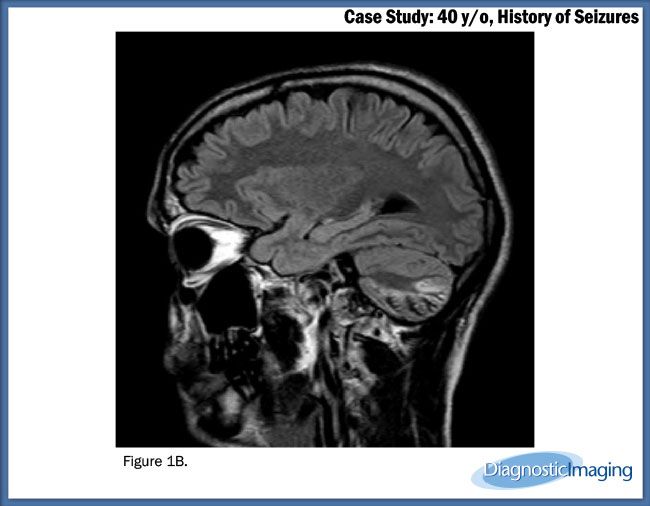

Case History: 40-year-old patient presented with history of seizures.

Case History: A 40-year-old patient presented with history of seizures.